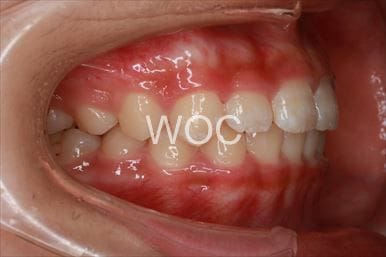

出っ歯舌側矯正

上下舌側矯正を希望。

通院状況や歯みがきの協力が良かったため、1年7ヶ月で治療を終えることができました。※装置と注意事項に関しては、大人の矯正装置一覧へ。

- 年齢:20歳女性

- 主訴:出っ歯が気になる

- 基本矯正料金:120万円

- 治療期間:1年7ヶ月

- 抜歯部位:上顎両側第一小臼歯